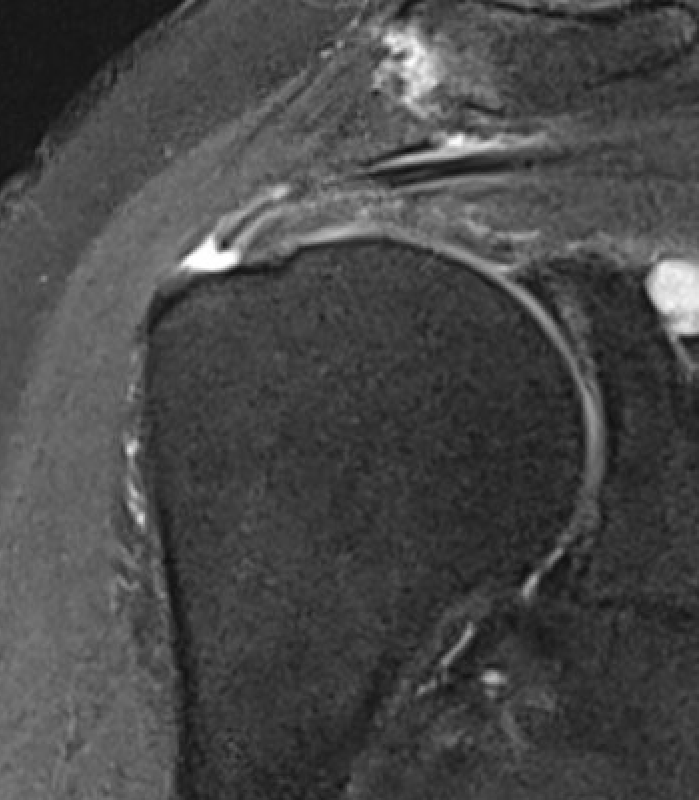

MRI

Look for

- supraspinatus / infraspinatus / subscapularis / long head of biceps pathology

- partial verus full thickness

- size of tear in coronal and sagittal planes

- retraction

- atrophy / fatty infiltration

Full thickness rotator cuff tears

Partial bursal sided tear Partial articular sided tears

Subscapularis tears

Small full thickness rotator cuff tear of supraspinatus - retracted to footprint

Large full thickness tear of supraspinatus and infraspinatus tendon - retracted to midhumeral head

Massive rotator cuff tear of the supraspinatus and infraspinatus tendon - retracted to glenoid